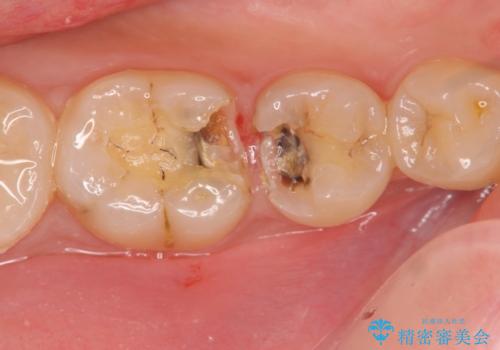

- 右上奥歯の虫歯を放置したのち他院にて抜歯、インプラント治療は難しいと言われ当院に相談・来院されました。

CT像より歯槽堤・顎骨が大きく欠損し、このままでは十分な骨量がなくインプラント埋入が難しい状態です。

インプラント埋入を予定するに先立って、歯槽堤の骨量の再建・上顎洞粘膜穿孔の修復・上顎洞底の挙上を行います。